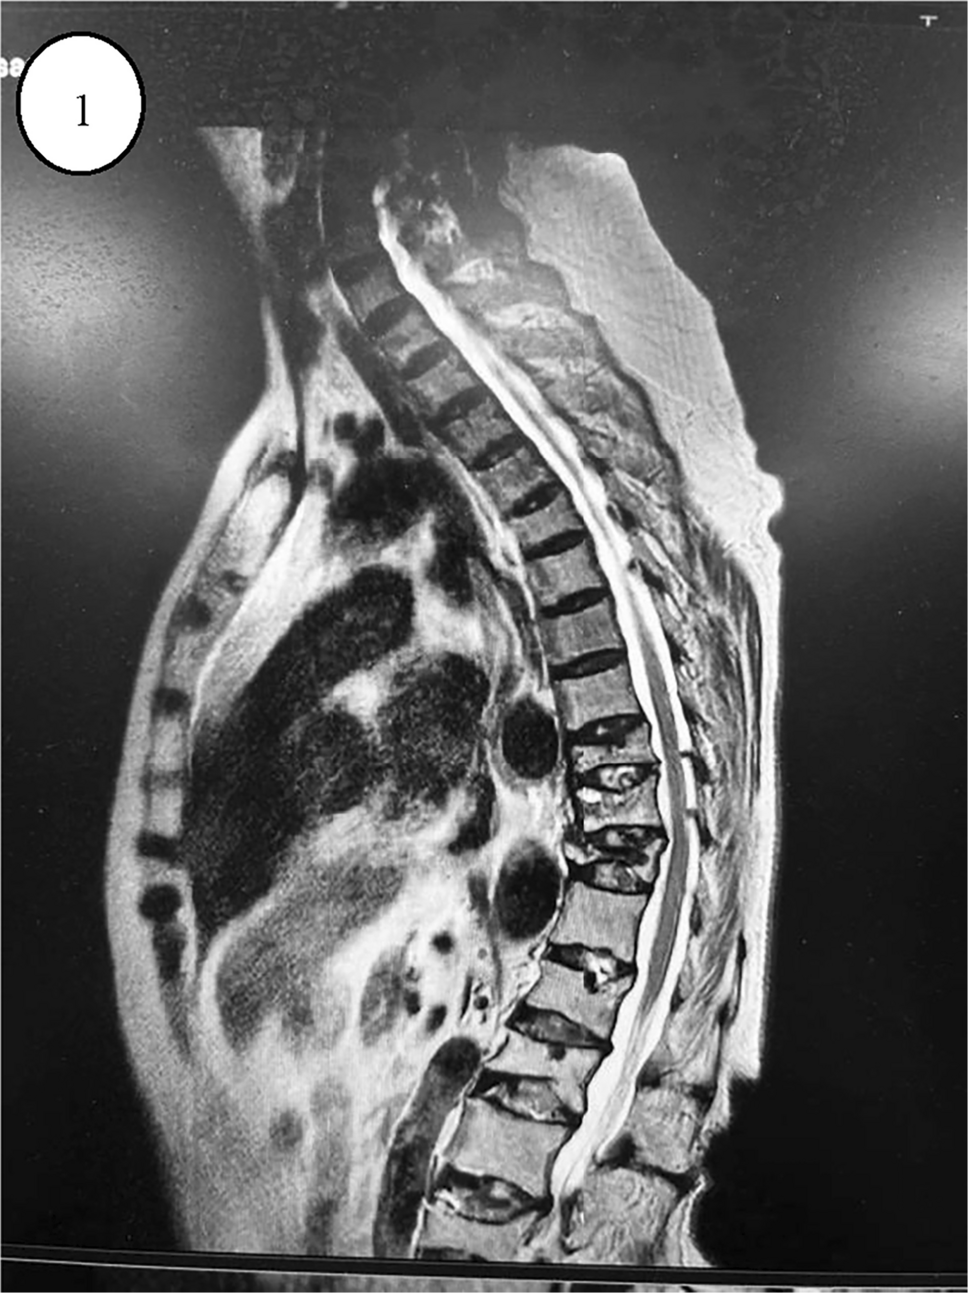

A 72-year-old female patient experienced a height reduction of 10 cm over 10 years and presented to our outpatient clinic in early November 2023 with severe back pain after an unstable standing twist. She had a history of coughing and sputum production for over 30 years, menopause at 49, and no other medical history. The patient's back pain and bilateral rib pain gradually worsened over a week, becoming more pronounced during activity and coughing, and alleviating with rest. Physical examination revealed: height 158 cm, weight 52 kg, visible spinal deformity, reduced chest-abdominal wall distance, and a bow-shaped kyphosis on spinal examination. Lung auscultation revealed moist rales. MRI indicated: 1. Fresh compression fractures of T9-11, with bone marrow edema changes in the T9 lamina; 2. Compression fractures of L1, 2, 4 (old); 3. Disc protrusion at L3/4, L4/5, and Schmorl's nodes formation at L1-4; 4. Osteoporosis of the thoracolumbar spine; thoracolumbar degenerative changes; subcutaneous fasciitis of the back as shown in Fig. 1. Dual-energy X-ray absorptiometry indicated: L1-4 bone density 0.560 g/cm2, T-score -4.4, Z-score -1.5, representing severe osteoporosis. To determine the cause of the patient's osteoporosis, serum levels of calcium, phosphorus, and parathyroid hormone (PTH) were checked: calcium, 1.85 mmol/L; phosphorus, 0.83 mmol/L; PTH, 81.20 pg/mL, all within normal ranges. Additionally, tests showed white blood cells, 5.22*10^9/L; red blood cells, 3.88*10^12/L; hemoglobin, 111 g/L; C-reactive protein, 3.33 mg/L; 25-hydroxyvitamin D, 16.30 ng/mL; thyroid-stimulating hormone (TSH), 1.2729 μIU/mL; urea, 4.47 mmol/L; creatinine, 41.2 μmol/L; aspartate aminotransferase, 20 U/L; alanine aminotransferase, 17 U/L; all immune series negative, ruling out hyperparathyroidism, hyperthyroidism, liver dysfunction, kidney dysfunction, and immune series diseases. Given her 30-year history of coughing and sputum production, a chest scan was completed, and paranasal sinus scan indicated: left maxillary sinusitis, slight deviation of the nasal septum, possible chronic bilateral otitis media; multiple small nodules in both lungs, slightly enlarged mediastinal lymph nodes; osteoporosis, uneven bone density of the manubrium, fracture of the left second anterior rib, sternal fracture, compression fractures of T6, L9, L10. She had a 30-year history of persistent coughing and sputum production, with paranasal sinus CT indicating chronic sinusitis, chest CT showing diffuse small nodular shadows as in Fig. 2, lung auscultation with moist rales, diagnosed as diffuse panbronchiolitis (DPB). After ruling out secondary factors and common pathogenic factors, it was suspected that her severe osteoporosis might be closely related to diffuse panbronchiolitis, and whether DPB could induce or exacerbate osteoporosis. Based on this hypothesis, the patient was treated with anti-osteoporosis and anti-inflammatory medications. Currently, her pain has alleviated, and she can perform daily activities, but she remains under continuous treatment.

Fig. 1

MRI showing spinal compression fractures